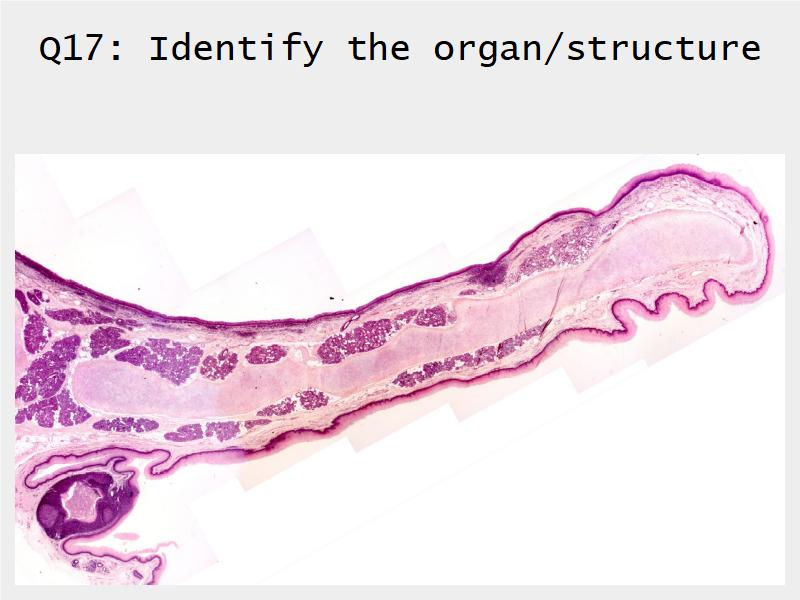

Respiratory Epithelium: Trachea

Today and Now I will do something for my future self.Trachea

- Slide 73: Trachea

Respiratory epithelium

- Pseudostratified

- Ciliated

- Columnar

- Epithelium with

- 4 Cells

- Ciliated columnar cells

- Non-ciliated columnar cells

- Goblet cells

- Basal cells